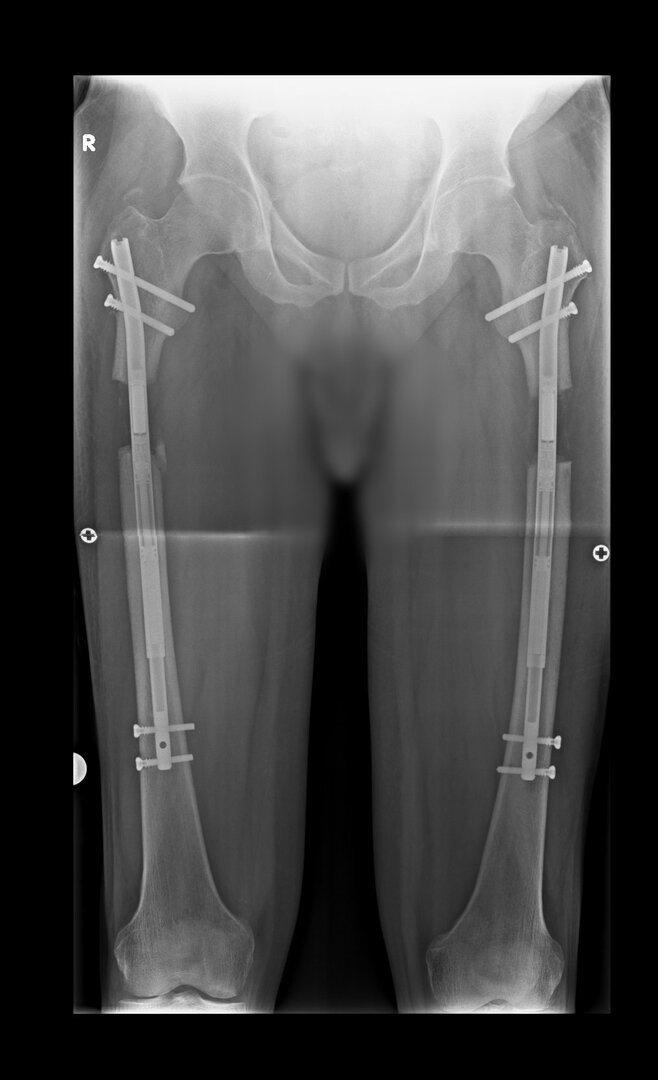

Görüntüleri büyütmek için üzerine tıklayınız.

Görseli büyütmek için üzerine tıklayınız. Görseli büyütmek için üzerine tıklayınız. Radyografi görseli büyütmek için üzerine tıklayınız. Radyografi görseli büyütmek için üzerine tıklayınız. Radyografi görseli büyütmek için üzerine tıklayınız.